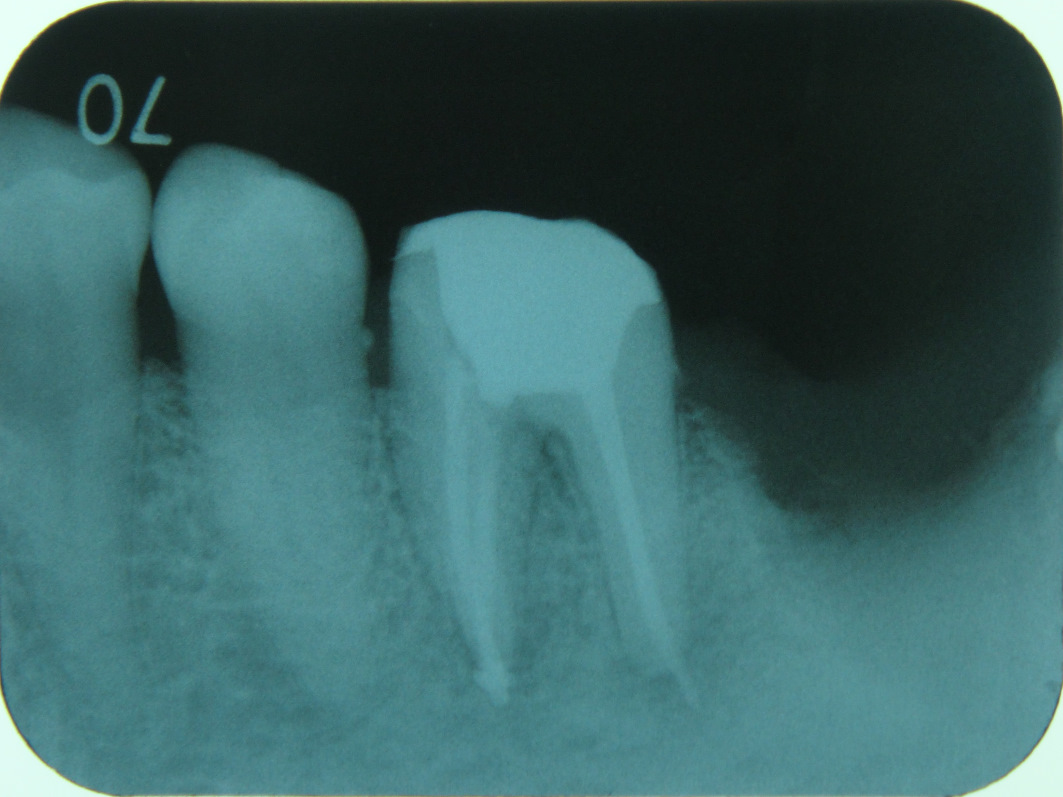

![]()

根管治療が終わったら、レントゲンで確認します。